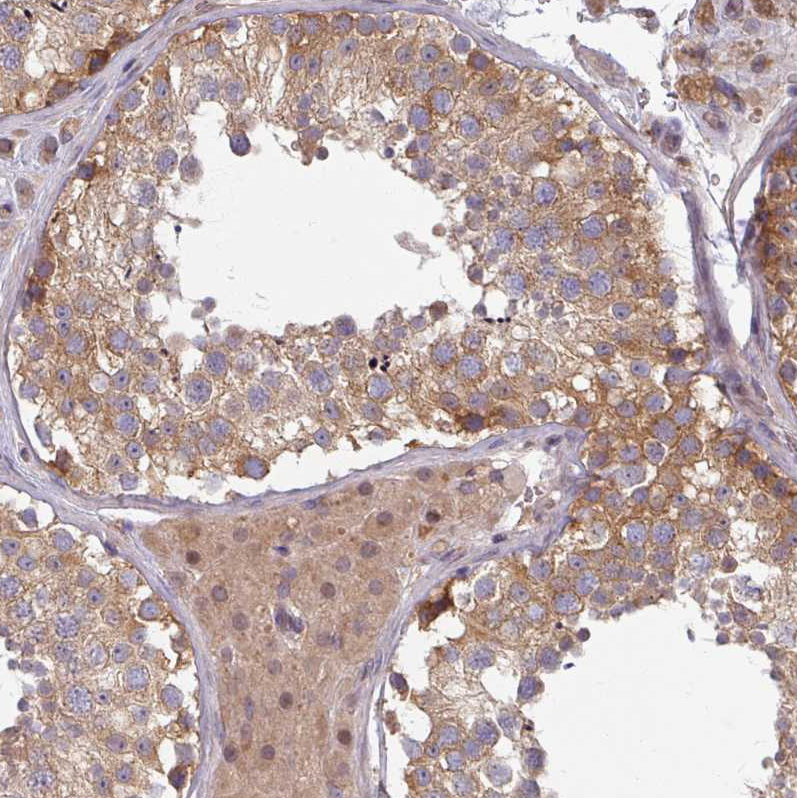

Immunohistochemical staining of human cerebral cortex shows moderate cytoplasmic positivity in neurons.